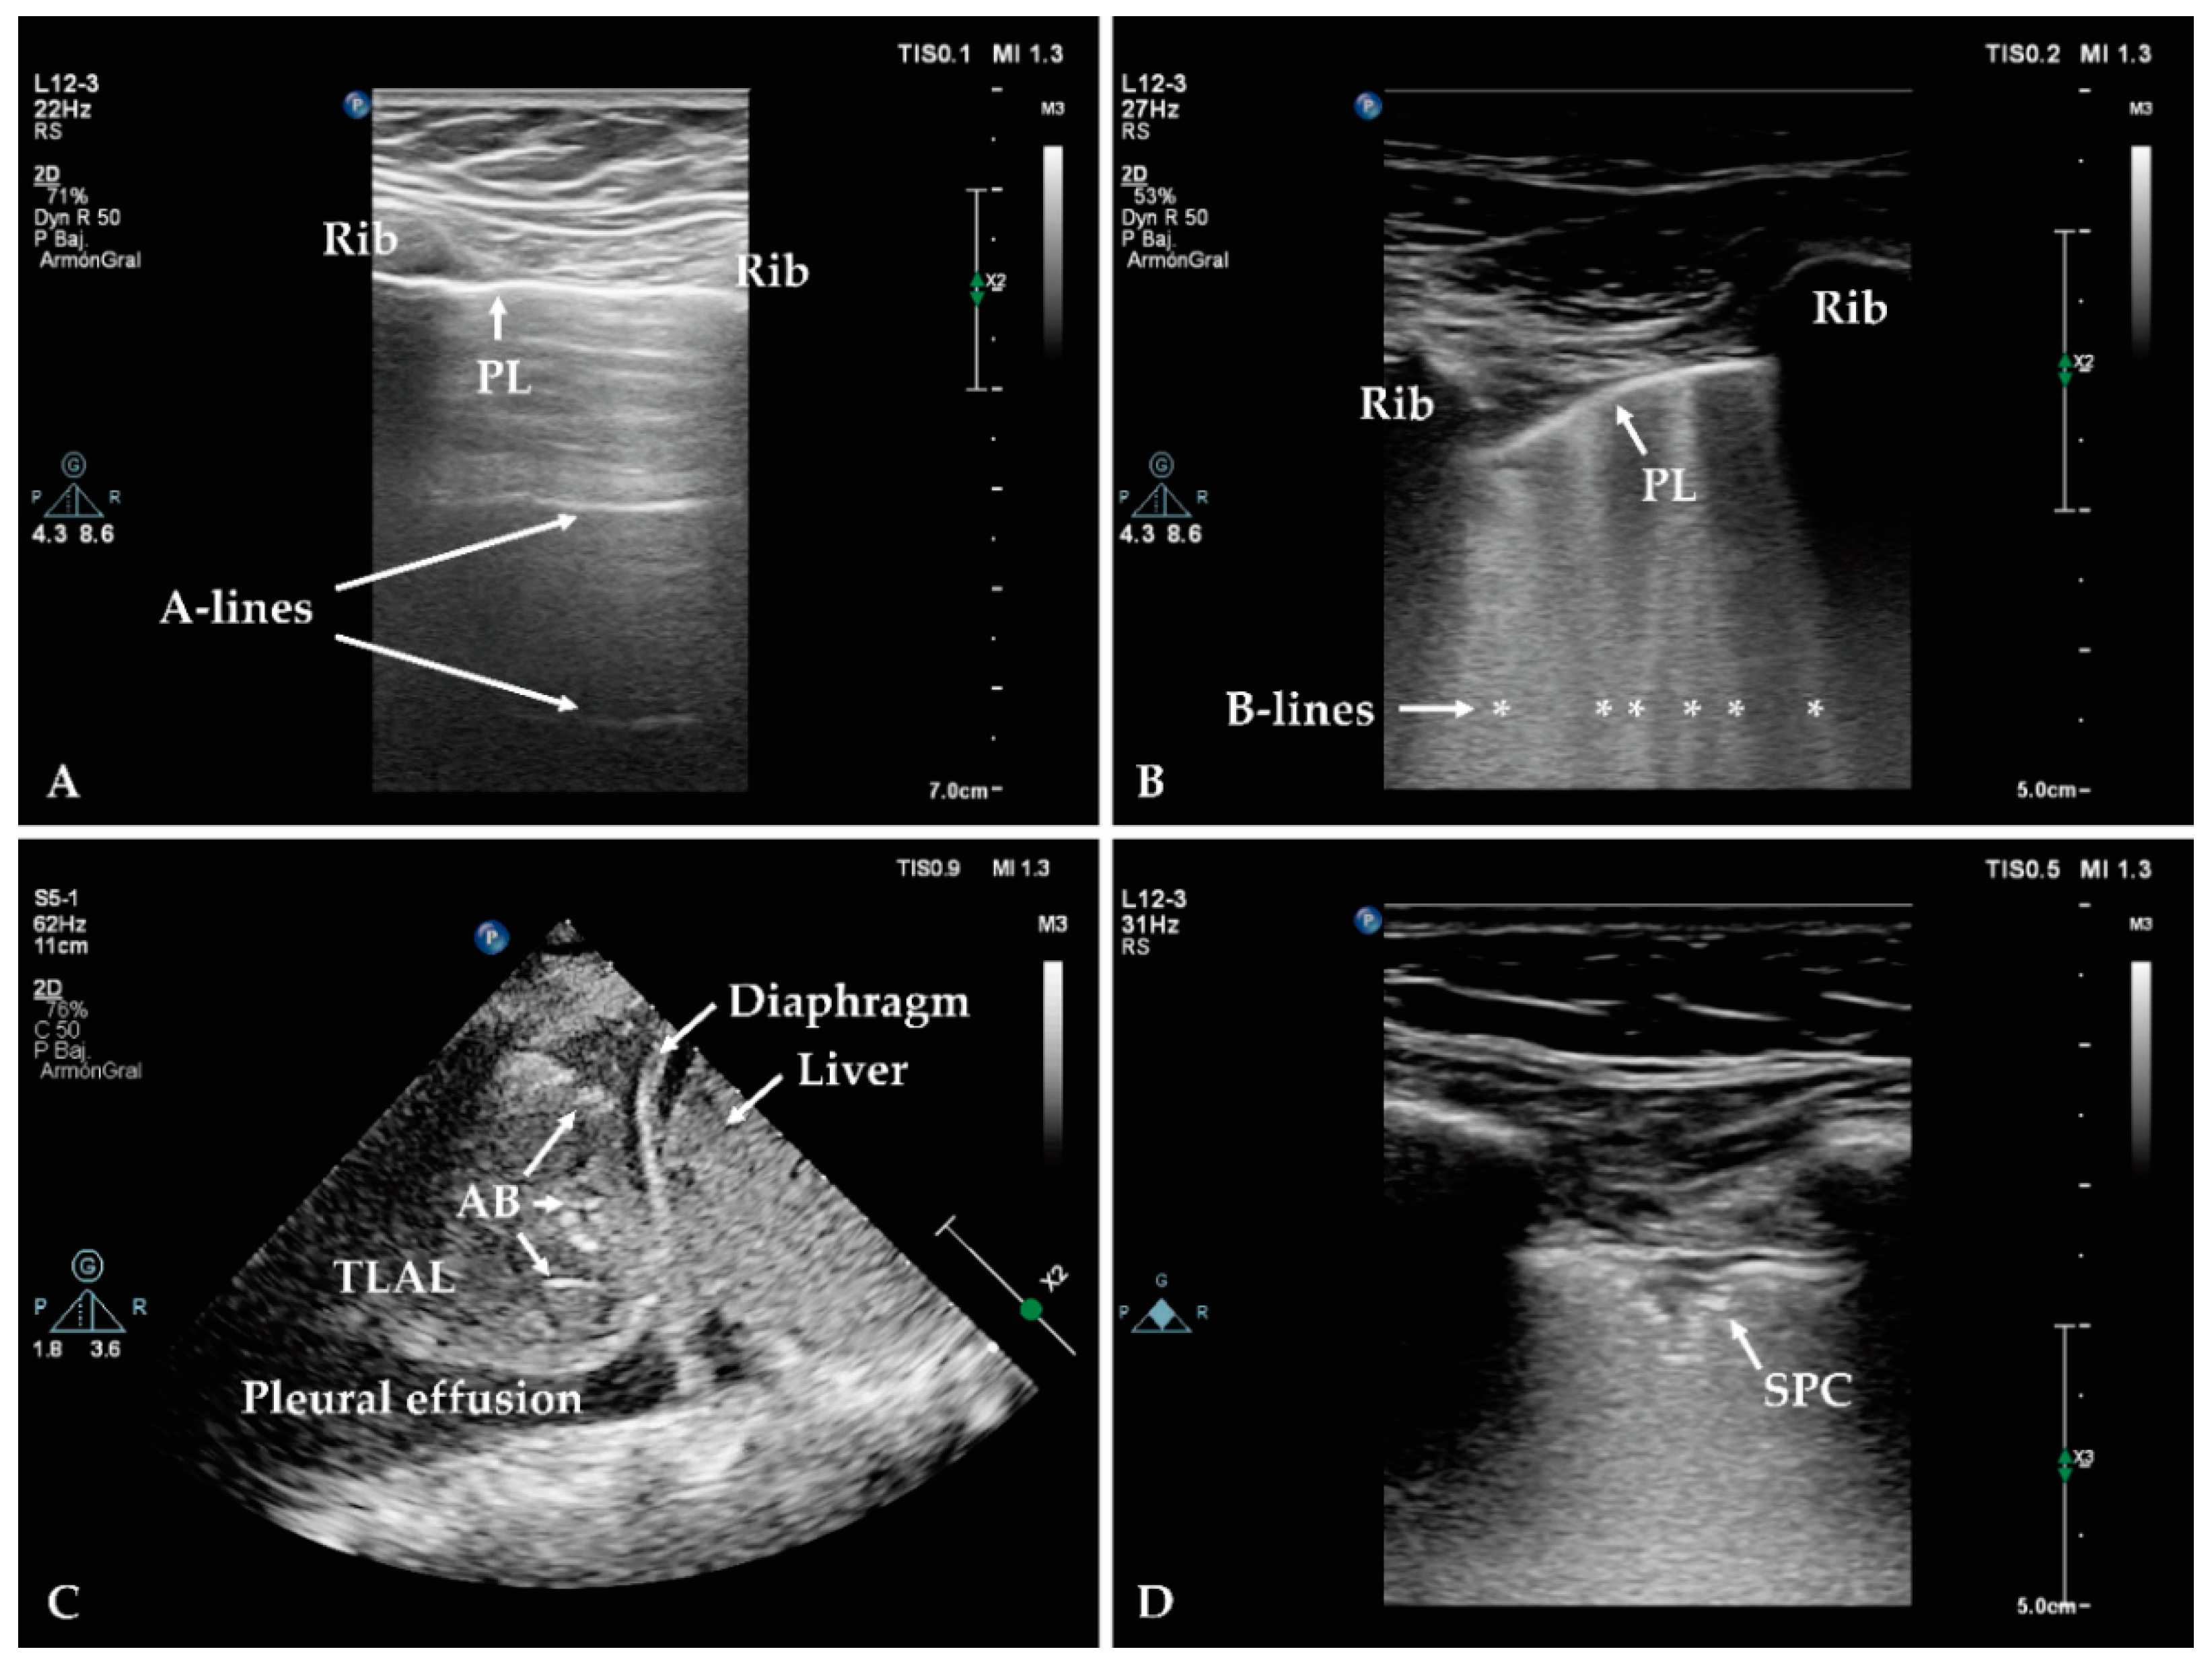

- Mojoli, F.; Bouhemad, B.; Mongodi, S.; Lichtenstein, D. Lung ultrasound for critically ill patients. Am. J. Respir. Crit. Care Med. 2019, 199, 701–714. [Google Scholar] [CrossRef]

- Lichtenstein, D.A.; Mezière, G.A.; Lagoueyte, J.-F.; Biderman, P.; Goldstein, I.; Gepner, A. A-lines and B-lines: Lung ultrasound as a bedside tool for predicting pulmonary artery occlusion pressure in the critically ill. Chest 2009, 136, 1014–1020. [Google Scholar] [CrossRef]

- Dietrich, C.F.; Mathis, G.; Blaivas, M.; Volpicelli, G.; Seibel, A.; Wastl, D.; Atkinson, N.S.; Cui, X.-W.; Fan, M.; Yi, D. Lung B-line artefacts and their use. J. Thorac. Dis. 2016, 8, 1356. [Google Scholar] [CrossRef] [PubMed]

- Lichtenstein, D.; Mezière, G.; Seitz, J. The dynamic air bronchogram: A lung ultrasound sign of alveolar consolidation ruling out atelectasis. Chest 2009, 135, 1421–1425. [Google Scholar] [CrossRef]

- Staub, L.J.; Biscaro, R.R.M.; Maurici, R. Emergence of Alveolar Consolidations in Serial Lung Ultrasound and Diagnosis of Ventilator-Associated Pneumonia. J. Intensiv. Care Med. 2019, 36, 088506661989427. [Google Scholar] [CrossRef]

- Bouhemad, B.; Dransart-Rayé, O.; Mojoli, F.; Mongodi, S. Lung ultrasound for diagnosis and monitoring of ventilator-associated pneumonia. Ann. Transl. Med. 2018, 6, 418. [Google Scholar] [CrossRef]